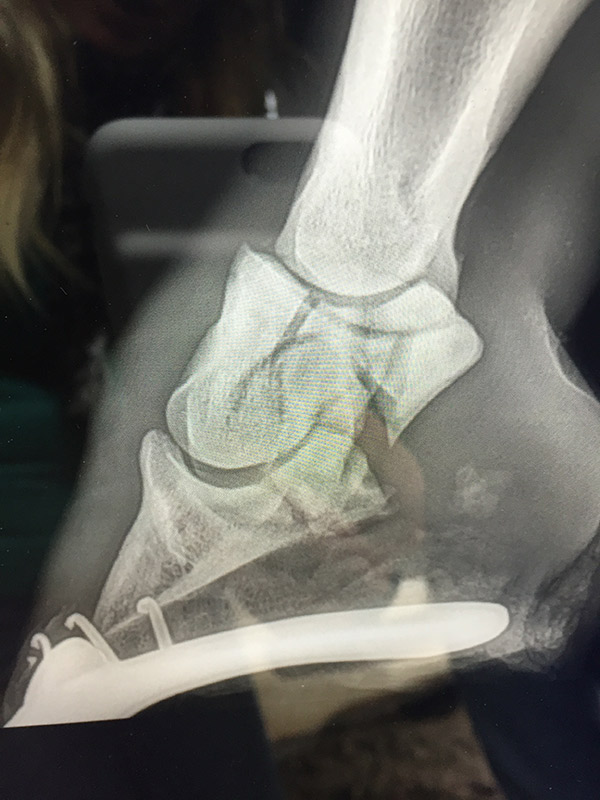

Radiología

Contamos con el equipo de radiología digital inalámbrico más avanzado del país, el cual permite obtener las mejores imágenes en el acto y compartirlas vía mail. Realiza radiografías de miembros, columna, cabeza, cuello y hombro.